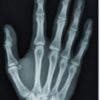

Upon examination, she had moderate swelling and tenderness over the dorsal aspect of the right third and fourth digits, with maximum tenderness over the level of the metacarpal heads (Fig. 1). Furthermore, an active range of motion causes pain and discomfort more pronounced with active extension. Her left hand was not swollen and was non-tender. Flexion at the MCPJ produced pain and ulnar dislocation of the extensor tendon at that level of the third and fourth digits in both hands. Moreover, she had ulnar dislocation of the extensor tendon of the right fifth digit. In full extension, the extensor tendons were centralized. She was treated conservatively by strapping the third and fourth digits, and a wrist splint was applied; she improved within 5 days.

Blood investigations were also done, including erythrocyte sedimentation rate, rheumatoid factor, and antinuclear antibodies, which were all negative. Plain X-rays at the time showed no fractures, dislocation, bony erosions, or arthritis.